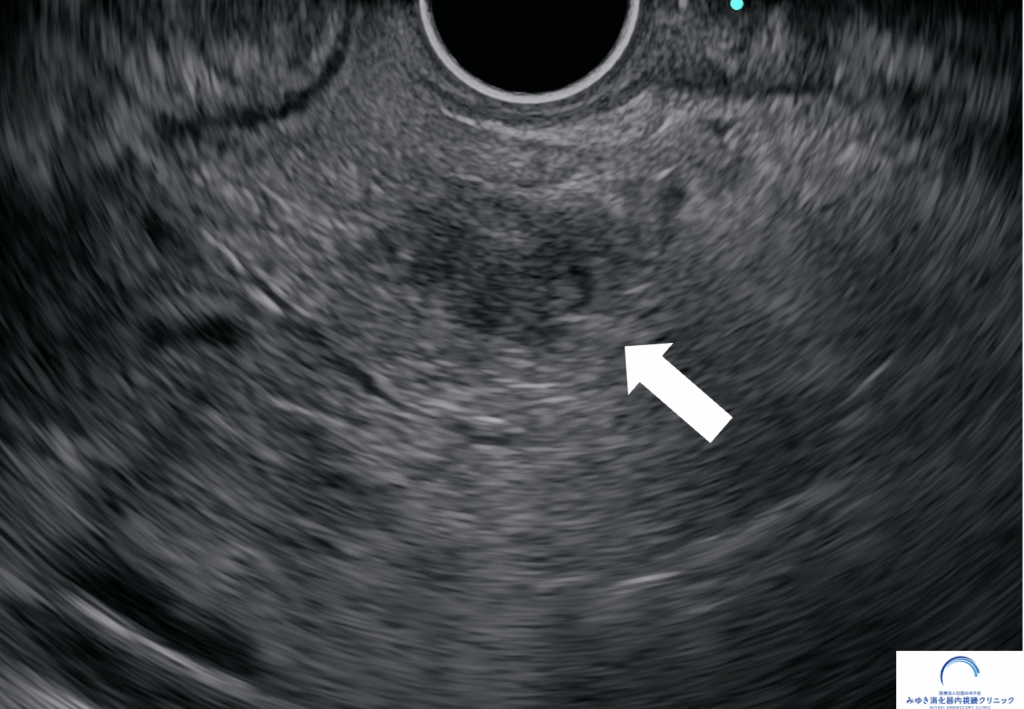

<膵神経内分泌腫瘍>

他院での腹部エコー、CT、MRIでは膵臓に異常を認めませんでしたが、当院での超音波内視鏡検査で10mmの腫瘤を認めました。超音波内視鏡せん刺吸引法(EUS-FNA)で神経内分泌腫瘍と診断しました。